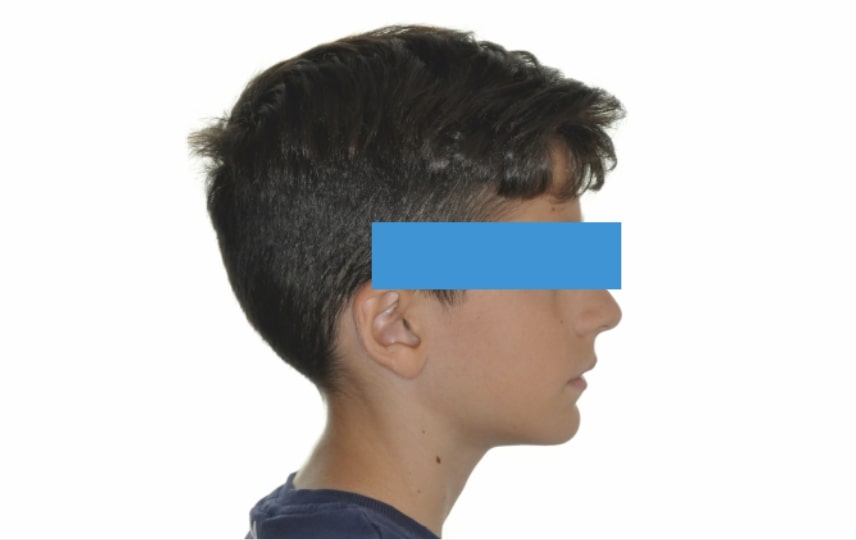

Age: 10 years old

Gender: Male

Section Class II division 1 malocclusion

FACIAL: class 2 profile with Lower jaw deficit